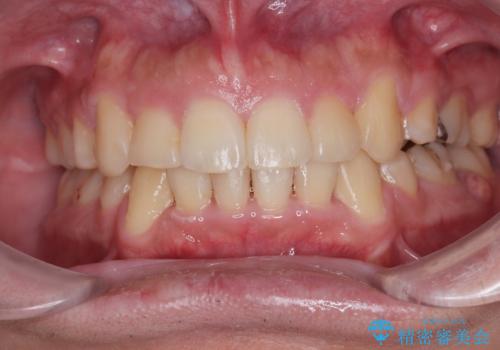

デコボコと口元の突出感を改善 抜歯矯正治療

患者様には辛抱強く治療にお付き合いいただき、すっきりとした口元に仕上げることができました。